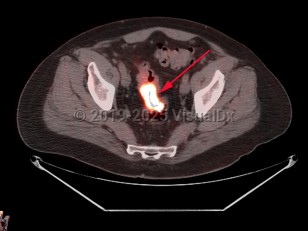

Rectal carcinoma

Patients with cancers of the rectum or rectosigmoid region often present with hematochezia, tenesmus, and narrowing of the stool. Anemia is uncommon at presentation.